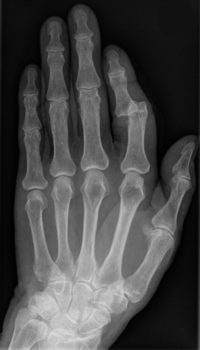

Röntgenbild eines ausgerenkten Zeigefingers

Bei einer Verrenkung oder Ausrenkung kommt es zu einer Verschiebung zweier durch ein Gelenk verbundener Knochenenden.

Dabei können die Gelenkpartner oft nicht mehr in die normalen Gelenkstellungen zurückkehren. Als Folge entstehen Kapsel- und Bandzerreißungen.

Sofortmaßnahmen

Datei:Ausgerenkter Ellbogen.jpg

Röntgenbild eines ausgerenkten Ellbogen

Pause, Entlastung, Hochlagerung, anschließend Transport ins Krankenhaus

Folgebehandlung

Schonende Einrenkung, evtl. mit Narkose durch den Arzt. Das Gelenk sollte für mehrere Tage geschont und entlastet werden. In der Rehabilitation helfen Mobilisations- und Kräftigungsübungen beim Heilungsprozess. Eine volle sportliche Belastbarkeit ist erst nach schmerzfreier Gelenkfunktion gegeben. Bei häufig wiederkehrenden Verrenkungen kann eine Operation erforderlich sein um dadurch eine bessere Gelenkstabilität zu erreichen.